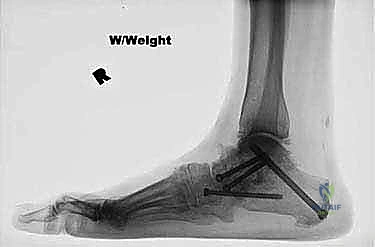

الخطوة الخامسة: التثبيت النهائي (Fixation)

بمجرد التأكد من المحاذاة المثالية للقدم، يتم استبدال الأسلاك المؤقتة ببراغي طبية قوية من التيتانيوم أو شرائح معدنية. هذه البراغي تضغط العظام معًا بقوة لضمان ثباتها التام حتى تندمج وتلتحم بمرور الوقت.

يتم استخدام جهاز الأشعة السينية المباشر داخل غرفة العمليات (Fluoroscopy) للتأكد من الموضع الدقيق للبراغي والمحاذاة المثالية للمفاصل.

الخطوة السادسة: وضع الطعوم العظمية (Bone Grafting)

لتحفيز وتسريع عملية الالتئام والاندماج، قد يتم وضع طعوم عظمية (أخذت من المريض نفسه من عظم الحوض أو الساق، أو طعوم صناعية) في الفراغات بين العظام.

الخطوة السابعة: إغلاق الجرح

بعد التأكد من التثبيت والاندماج المبدئي، يتم غسل المنطقة جيداً بمحاليل معقمة، ثم يُغلق الشق الجراحي الإنسي الواحد بعناية باستخدام خيوط تجميلية لتقليل الندبات، وتوضع القدم في جبيرة خلفية مبطنة جيداً.